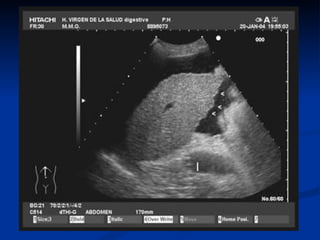

Diagnóstico por Imágenes.

   Ecografia.

   Eco-Doppler.

   T.A.C.

   R.M.N.

Ecografía

   Es el método de elección.

   100 ml de líquido ascítico.

Goldberg BB, Goodman GA, Clearfield HR. Evaluation of ascites by ultrasound. Radiology

1970;96:15-22.

   T.A.C.:

•     Enfermedad Pancreática.

•     Tumores.

•     Ascitis Quilosa ( Linfoma-Cáncer).

Eco-Doppler

   Trombosis Portal.

   S.Budd-Chiari.